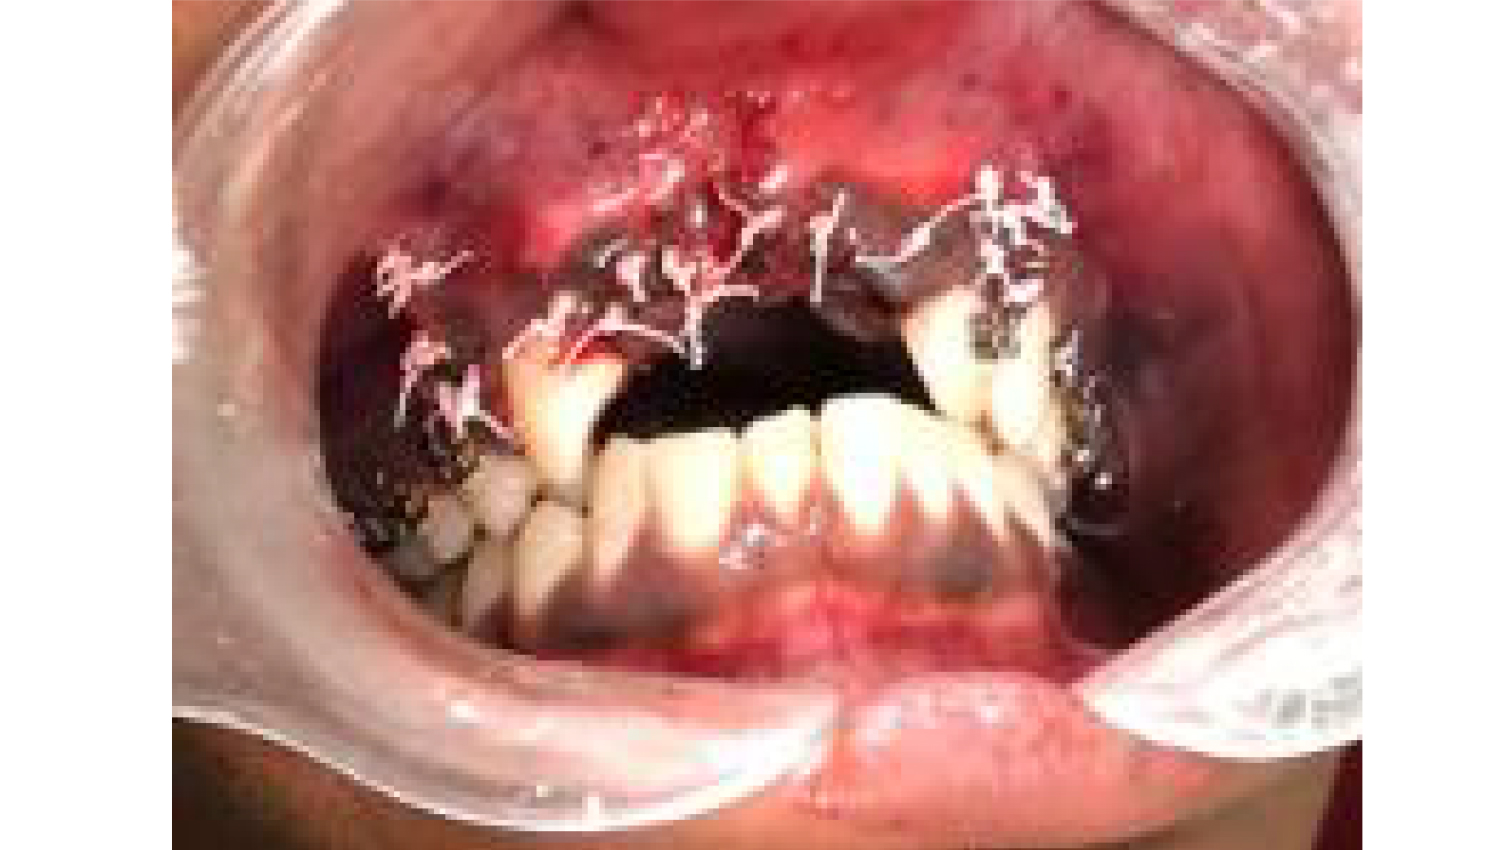

1.Initial clinical view.

2.Complex Three Dimensional Augmentation procedure was applied to the patient with Khoury's Technique. Powerbone Gel and Cortical plate products were used during the process.